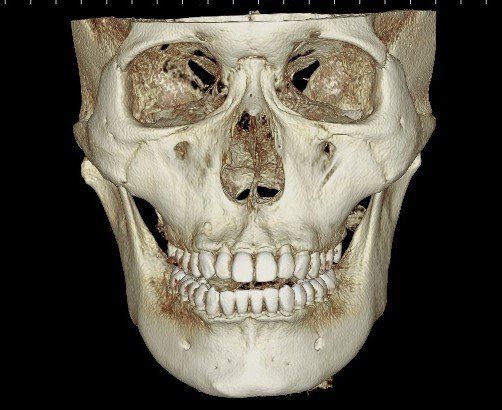

치아CT사진

정면CT사진1

4. 치아 문제라기보다는 골격적인 부분이 동반되어 있어 교정을 하더라도 개선이 어려울 수 있으며 완전한 교정을 위해서는 양악 수술을 해야할 수 있어 보입니다. 턱 자체가 비대칭입니다.